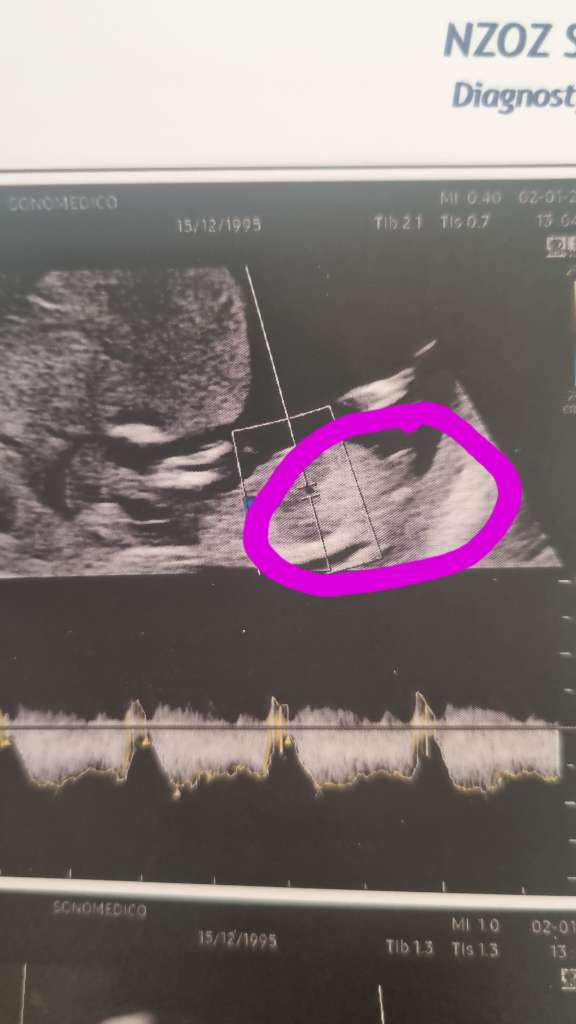

Czy widac tytaj wyrostek płciowy?

Hej , wróciłam z prenatalnych . Jak sądzicie jaka płeć nam się tu chowa ?

• 1ee867b3-da7f-4d58-84c8-ccf3b3700b6b.jpeg

1ee867b3-da7f-4d58-84c8-ccf3b3700b6b.jpeg

36 KB · Wyświetleń: 101